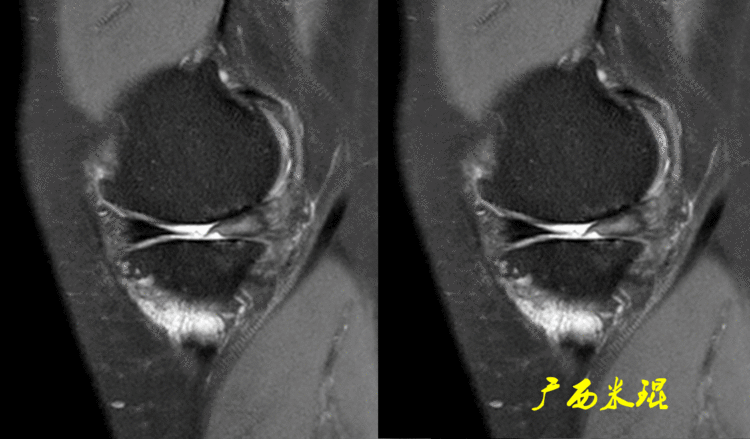

有时候我们在MR上看见内侧半月板信号正常,半月板体部呈单裙边改变,周围软骨正常。

有时候半月板体部呈双裙边改变,周围软骨正常,以上这样的情况半月板都是正常的,不是损伤。